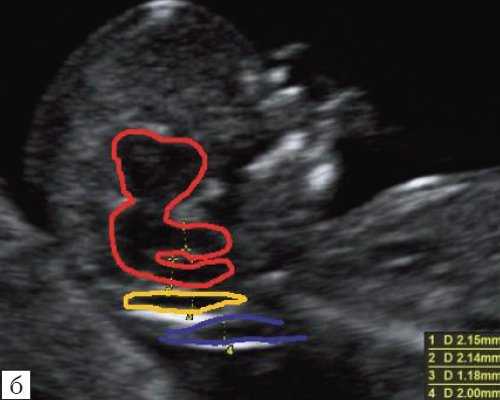

Новый ультразвуковой маркер в изучении нормальной ультразвуковой анатомии головного мозга плода в срок 11-14 недель беременности

Особенности визуализации изложенных выше структур в данном сроке позволили нам выделить и назвать новый ультразвуковой маркер нормальной ультразвуковой анатомии мозга плода. Структуры головного мозга плода в этой области схожи с осьминогом, у которого есть голова и две приблизительно равновеликие по диаметру ножки, представляющие собой ствол мозга и IV желудочек. Ниже ножек "осьминожки" визуализируется 2 "подушки осьминожки" - это два анэхогенных пространства - большая цистерна и воротниковое пространство (рис. 2, б).

Так как речь идет о сроках первого скрининга, т.е. раннего осмотра, новый ультразвуковой маркер мы назвали "осьминожкой" (рис. 3).

Как сказано выше, имеет значение и измерение ножек "осьминожки", так среднее значение диаметра нижней ножки, т.е. IV желудочка в зависимости от КТР в срок 11-14 недель варьирует от 1,5 до 2,5 мм (рис. 4).

Рис. 4. Измерение и взаимоотношение ножек "осьминожки" - ствола мозга и IV желудочка у плода, беременность 12 недель.

Измерение ножек "осьминожки".

Красный цвет - диэнцефалон (таламус), со стволом мозга (верхняя ножка) и IV желудочком (нижняя ножка); желтый цвет - большая цистерна головного мозга; синий цвет - воротниковое пространство.